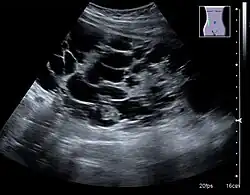

The complex cyst can be further evaluated with doppler ultrasonography, and for Bosniak classification and follow-up of complex cysts, either contrast-enhanced ultrasound (CEUS) or contrast CT is used.[13]

Renal ultrasonography of a simple renal cyst with posterior enhancement. -